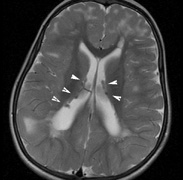

In young children, nearly half of sporadic cases fail to meet NIH criteria by 1 year of age, but meet them by age 8 to 12 years. The clinical features appear in the following order: café au lait spots, axillary freckling, Lisch nodules, neurofibromas.26 The inclusion of UBOs on MRI also aids the diagnosis of very young children25 but may require a general anesthetic. Genetics and Screening All family members of patients with NF1 should be screened. Lisch nodules are present in 90% or more of patients with the disease, so ophthalmic examination is essential. Annual ophthalmic examination with visual acuity, visual field, color vision, and fundoscopy is recommended for affected individuals. The NF1 gene (17q11.2) was cloned in 1990.76,77 Its protein, neurofibromin, is expressed throughout the body but particularly in the central and peripheral nervous system.12 It is a tumor-suppressor gene with autosomal dominant inheritance, high penetrance, and variable expressivity. NF1 has been called a neurocristopathy, but the disease is not limited to neural crest derived tissues.12,78 Neurofibromin has structural similarity to GTPase, activating proteins that inhibit the function of G proteins such as Ras. Inhibition of Ras by neurofibromin has been shown in vitro and in vivo. NF1-deficient tumors show increased levels of Ras-GTP. Increased Ras function has been shown in a number of human tumors.12,79–81 NEUROFIBROMATOSIS TYPE 2 Neurofibromatosis type 2 (NF2) was described in 1822 by the Scottish surgeon Wishart.82 Initially, NF1 and NF2 were lumped together despite their differences.83 The identification of different genes re-established them as separate entities.84 Epidemiology The NIH consensus conference22 estimated an incidence of 1:50,000 but there are varying estimates internationally.84 NF2 is autosomal dominant with full penetrance by age 60.85 In all, 10% of affected patients are symptomatic by age 10, 50% by 20 years, and 80% by 30 years.86 Some sporadic cases reflect parental mosaicism.87,88 Systemic Features Several studies have established the clinical picture of NF2.85,89–91 Patients may become severely disabled because of the combination of deafness and imbalance from vestibular schwannomas, weakness from multiple spinal tumors, and poor sight from cataracts, optic nerve meningiomas, and retinal hamartomas. CUTANEOUS FINDINGS. Skin findings in NF2 may be subtle but not uncommon. Skin tumors were found in 60% and were the first presenting sign in more than 25% of patients.92 The skin tumors are predominantly schwannomas. A minority are neurofibromas and mixed types. Clinically differentiating the histological types may be difficult.92 They may present as dermal tumors or subcutaneous nodules of peripheral nerves. NF2 plaques are well circumscribed, slightly raised, often pigmented, and hairy. They are a sensitive marker for NF222 and are more common on the limbs and trunk than the neck and face.92 Café au lait spots are not uncommon in NF2, but it is unusual to find more than five and most tend to be restricted to the trunk. Plexiform neurofibromas and axillary/inguinal freckling are uncommon.92,93 NEUROLOGIC FINDINGS.

Neurologic Findings INTRACRANIAL LESIONS. Mental retardation and seizures in TSC are often associated with benign CNS astrocytic hamartomas.131 On imaging, the cerebral lesions show three patterns:132